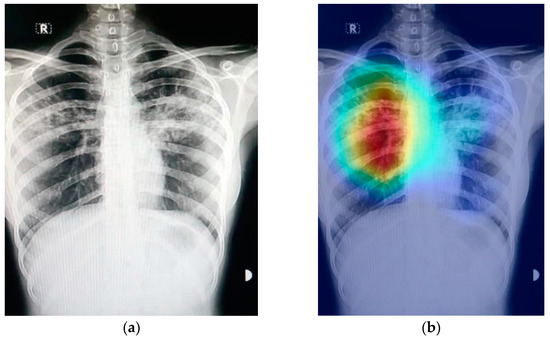

No description has been provided for this image Interpretabilidade em CNNs. Fonte: Umair, Muhammad, et al. "Detection of COVID-19 using transfer learning and Grad-CAM visualization on indigenously collected X-ray dataset." Sensors 21.17 (2021): 5813.

• O que é CAM?: Uma técnica para gerar mapas de ativação que indicam as regiões discriminativas de uma imagem usadas pela CNN para identificar uma categoria específica.

• Explicabilidade Visual: O resultado é um mapa de calor (heatmap) que visualiza onde a CNN está "olhando" ao fazer uma previsão.

• O CAM permite a localização de objetos (desenhar uma caixa delimitadora) usando apenas rótulos de nível de imagem (classificação), sem a necessidade de anotações de caixas delimitadoras (bounding boxes) durante o treinamento.

• Sobreposição: A sobreposição da imagem original com o mapa de calor visualiza as regiões discriminativas.

• Note que o CAM foca apenas nas ativações da última camada convolucional, que pode ser mais propensa às características de alto nível, mas ignora as representações localizadas de camadas mais rasas.